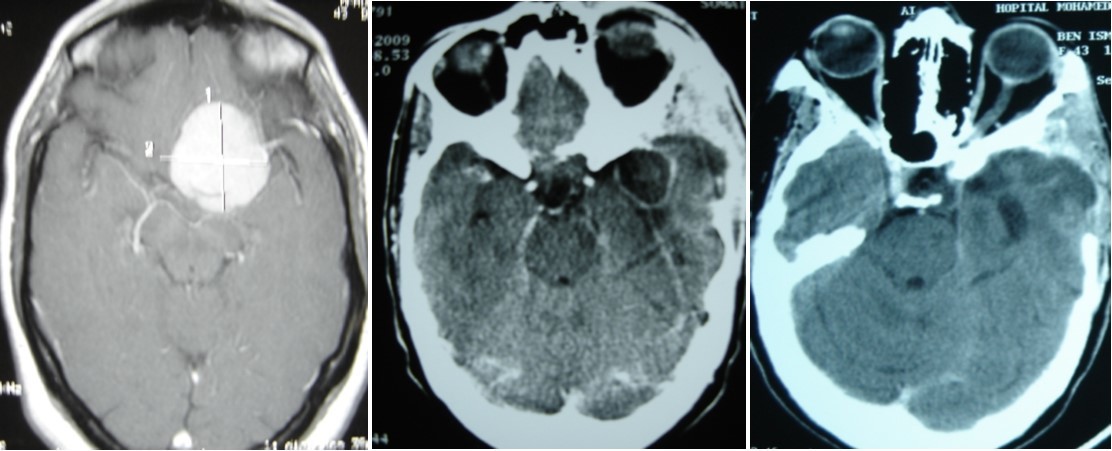

A 65 year-old man presented with progressive visual decrease and ptosis in the left eye. Neurological examination revealed paresis of the 3rd left cranial nerve. Fundoscopy revealed bilateral papillary paleness and visual acuity was: 4/10 at left; 7/10 at right. No signs of endocrine insufficiency or hypersecretion were assessed. There was no evidence of sinusitis. Chest X-ray, routine laboratory investigations and hormonal blood tests were normal. A CT scan showed a hypodense mass enlarging the sphenoid sinus and sellar region with calcification like images and bone erosion of the sellar floor (Figure 5). MRI showed a mass of 26 mm x 33 mm x 25 mm in the sphenoidal sinus ans sellar region, with hypersignal intensity in T1-weighted (Figure 6A) ans T2-weighted sequences, and hyposignal zone in T2-weighted sequences (Figure 6B). Imaging investigations were suggestive of unusual pituitary macroadenoma. The patient underwent a transnasal transsphenoidal approach for excision of the mass. A yellow-brownish gluey material with gummy debris was aspirated from the sphenoid sinus, which was completely cleaned. The sellar floor was eroded which allowed a view of the intact inflammatory dura. An intra-operative presumptive diagnosis was made of caseating granuloma (i.e tuberculosis). The post-operative course was uneventful: the patient recovered from ptosis and visual acuity improve at discharge. Mycobacterium tuberculosis could not be cultured from specimens; and cultures on Sabouraud’s medium did not isolate Aspergillus. Pathologic findings were of non invasive aspergillosis, with many septated fungal hyphae being present without tissue invasion. The patient was not given antifungal drugs because the intrasphenoidal material was completely aspirated. At 6 month and 18 months follow up, the patient had no neurological complaint. No recurrence was observed on control CT scans.

Figure 5.CT scan showing a hypodense mass enlarging the sphenoid sinus and sellar region with calcification like images and bone erosion of the sellar floor

Figure 6.(a) Sagittal T1-weighted MRI showing a well circumscribed hyperintense process in the sphenoidal sinus and sellar region; (b) parasagittal T2-weighted MRI showing a regular hypointense zone into the hyperintense process which is specific to aspergillus infection and corresponds to iron accumulation

A 45 year-old woman, operated 6 months before for left sphenoid wing meningoma revealed by raised intracranial pressure, with hemiplegia. She underwent surgery, with simpson I resection. The post operative outcome was good and the patient was discharge. Six months later, she presented a swelling on surgical site of skin incision. Blood check found inflammation with raised C-Reactive Protein. CT scan permitted to suggest brain abcess and she was operated in emergency with bone flap removal and the abscess complete excision. Bacteriologic and Histologic examination of the pus, revealed aspergillus flavius. The patient was treated by amphotéricin B because it was the antifungal avalailable in the hospital officine. Two months treatment was necessary to controle cerebral aspergillosis (Figure 7) and the patient was discharged with good outcome.

Figure 7.(A) pre operative MRI, axial T1 weighted with enhancement of sphenoid wing meningioma. (B) Ct scan showing an brain abscess in post op area. (C) CT scan after remoral sugery and 2 months medical treatment.